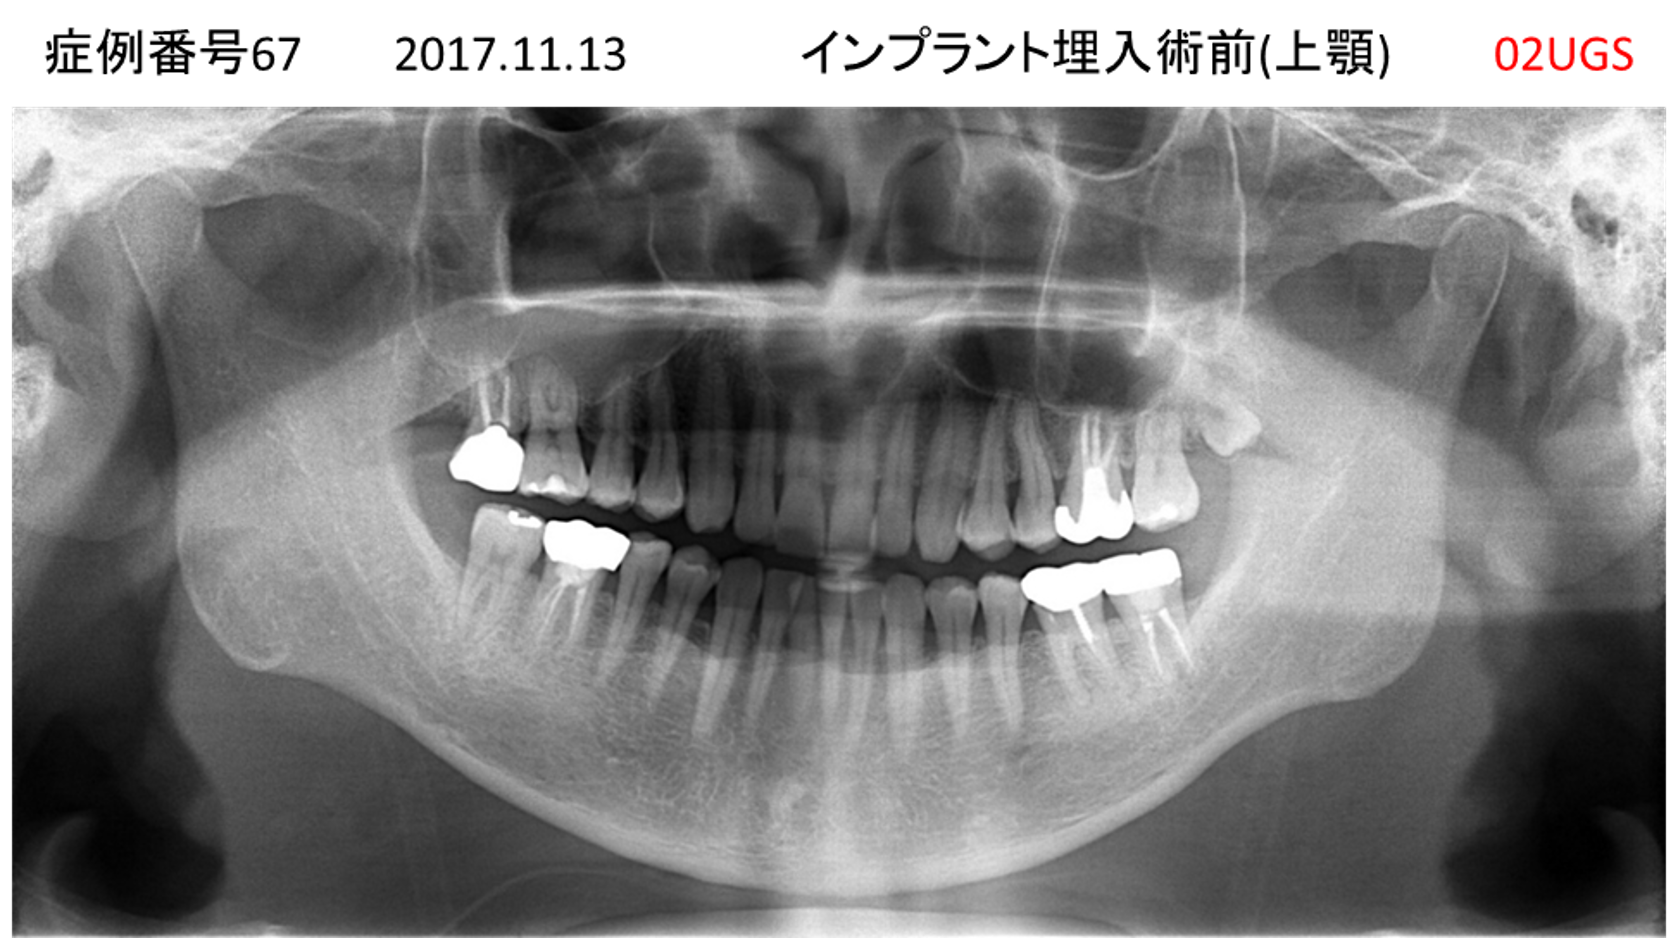

上の前歯が揺れてきてかめない患者様のインプラント症例

| 治療名称 |

インプラント |

| 治療費用 |

440万円+税 |

| 治療期間 |

6か月 |

| 患者さんの症状(主訴) |

上の前歯が揺れてきた。かめない |

| 治療内容 |

サイナスリフト、GBR、インプラント、即時荷重 |

| 治療結果 |

上の前歯の揺れが収まった。奥歯でしっかり噛める。 |

| 治療の注意点(リスク/副作用) |

インプラントが壊れたら再治療が必要 |